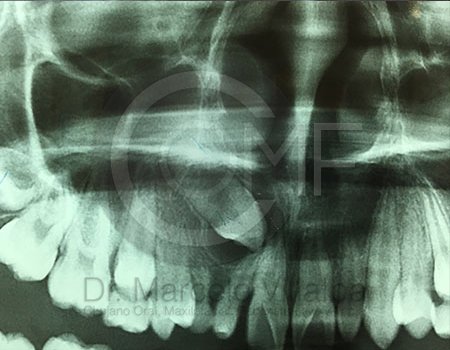

La Cirugía Oral y Maxilofacial es una de las especialidades odontológicas que brinda la posibilidad de ofrecer soluciones medicas y quirúrgicas a diferentes problemas de salud, entre los que se encuentran los defectos congénitos como el labio y paladar fisurados, las disarmonias del desarrollo facial, los traumatismos y lesiones patológicas de la región oral y maxilofacial por mencionar algunos; utilizando distintos procedimientos como la Cirugía Ortognática, la Reconstrucción mediante toma y colocación de injertos, distractores osteogénicos, regeneración tisular, implantes, etc.

Contenido Sensible y Gráfico

Si usted no pertenece al área de la salud, las imágenes pueden ser muy explícitas.